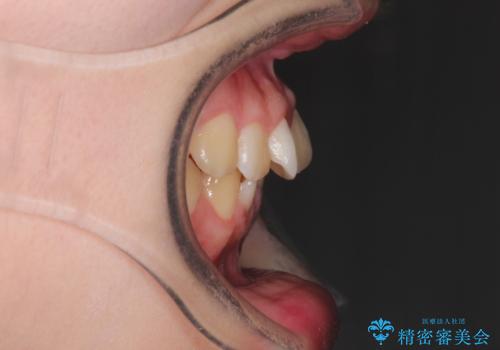

- 上下の歯並びを治したいとのことで来院されました。

受験生ということもあり、なるべく通院回数を減らしての矯正を希望されたので、インビザラインで治療をすることにしました。

ワイヤー矯正が1か月に1回程度来院が必要なのと比較すると、2-3か月に1回の来院でもよいので(症例によります)、通院回数を減らすことができて、患者様の負担を減らすことができます。